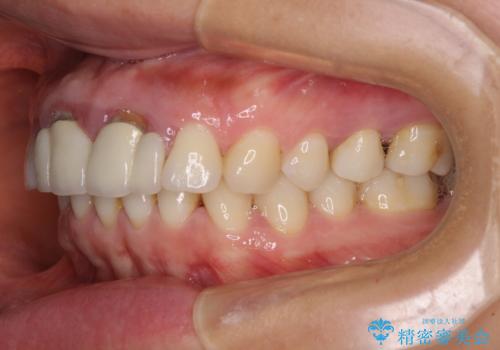

隙間をセラミックで閉じたら不格好で歯肉から出血 矯正治療と歯周外科で綺麗な前歯に

- 隙間の空いた前歯をセラミッククラウンで補隙したところ、歯肉から出血してしまい、何とかしたいとのことで来院された患者様です。

初めは前歯のみの処置で改善を希望されていたため、広範囲に処置範囲を広げることで歯の幅がバランスする治療を提案しましたが、削らなければならない歯が増えてしまうため、患者様と相談して全顎矯正により前歯のスペースを閉じていくこととしました。

不適合なクラウンが装着されていたため、歯周ポケットが深くなっていましたので、矯正治療前に歯周外科処置を行って歯周ポケットを除去し、矯正治療後にオールセラミッククラウンにて補綴治療を行うこととしました。